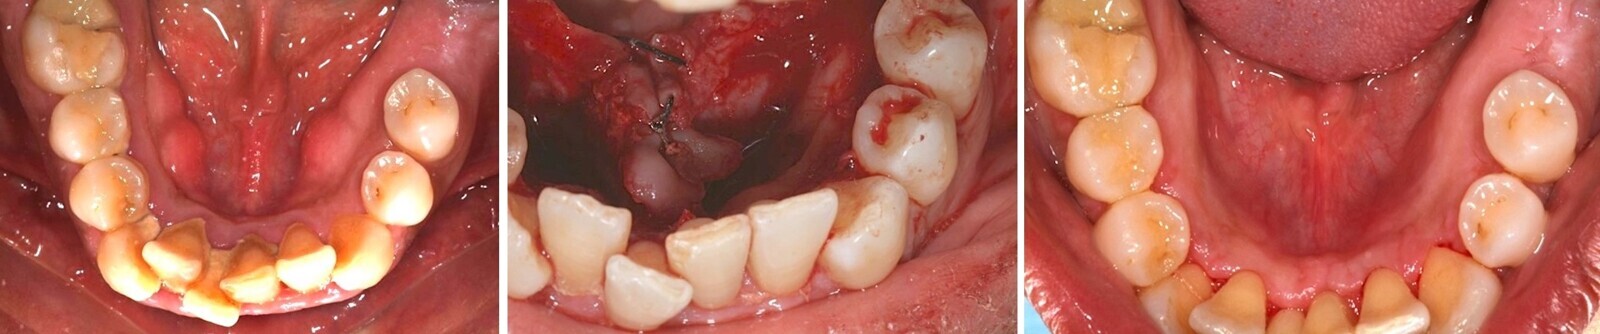

Además, produce un buen corte en los tejido duros dentales (Figuras 14-16), lo que ofrece una serie de ventajas10.

El corte de los tejidos duros dentales con el láser Er,Cr:YSGG ofrece una serie de ventajas (ver Figuras 14-16).

Fig. 14.

Fig. 15.

Fig. 16. Las figuras 14-16 muestran los cortes precisos que los láseres de erbio permiten realizar en los tejidos duros dentales.